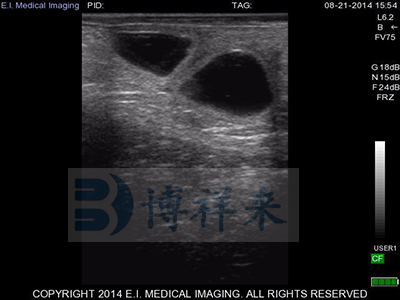

L7HD 高频线阵直肠探头(5-9MHZ可变) 高清分辨率

适用对象:牛马骆驼等大动物生殖检查、肌腱检查、新生犊牛肺部检查。